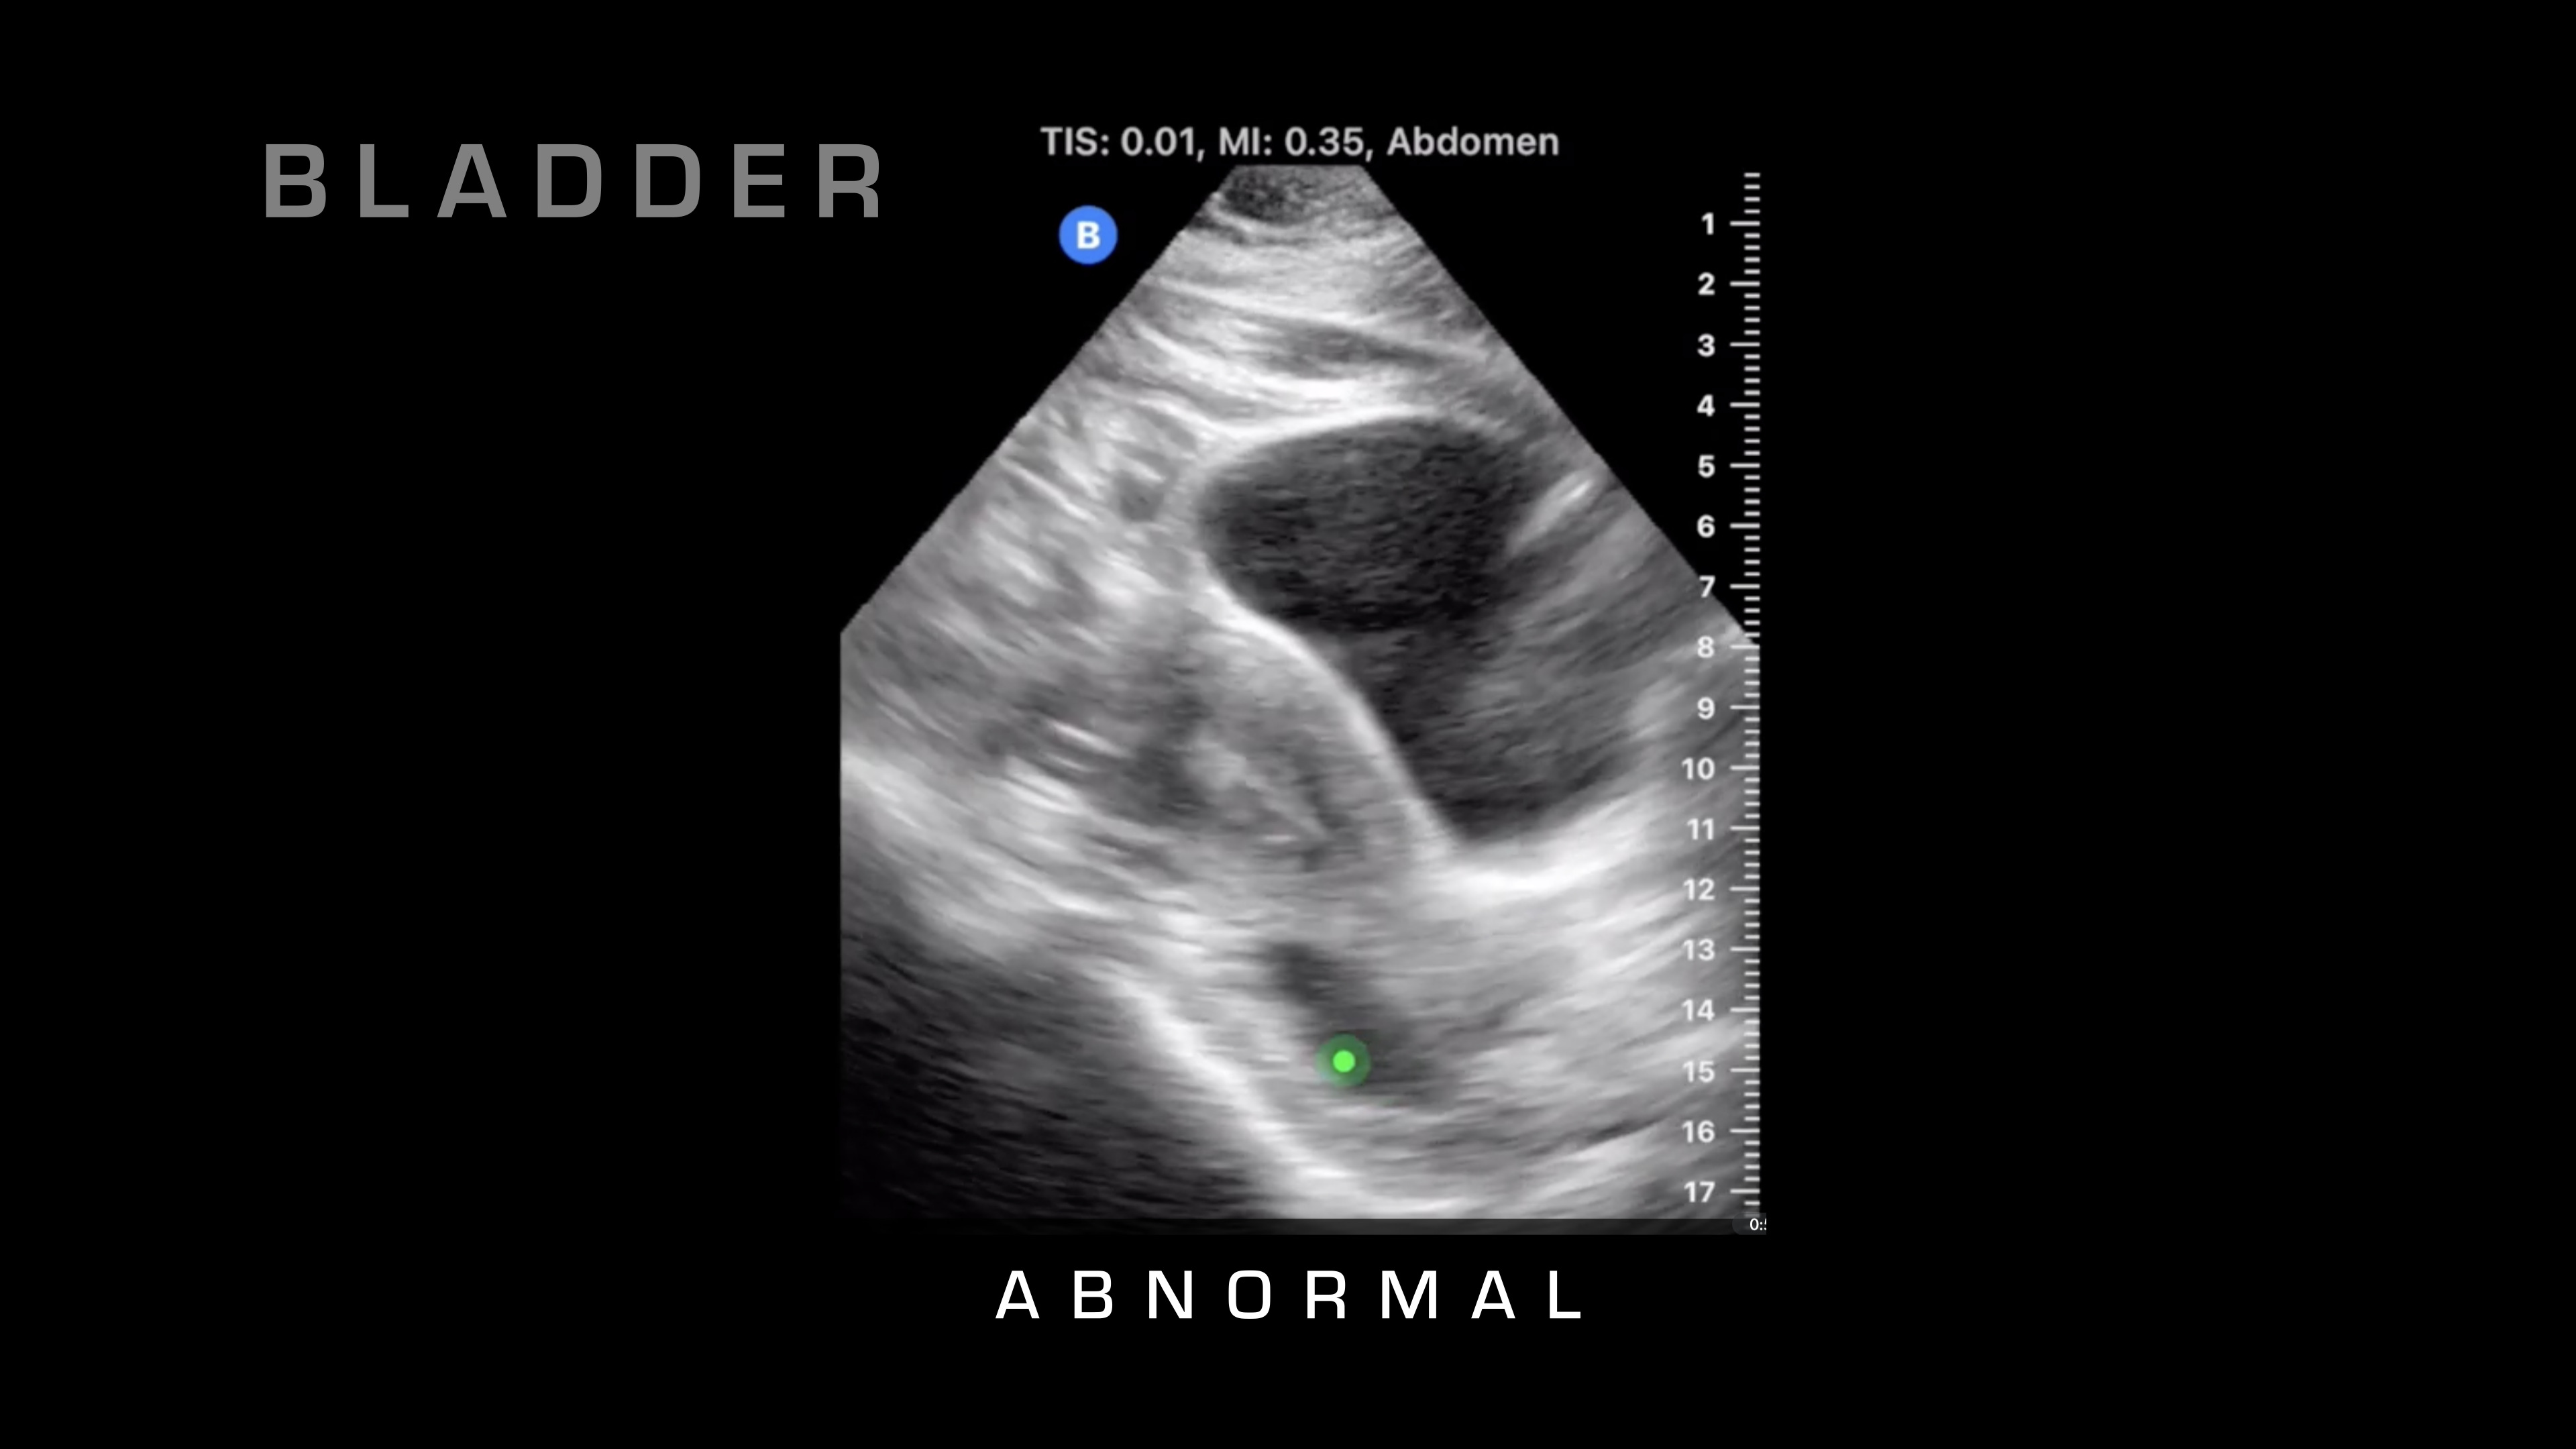

Pubic Symphysis

The next spot that I'm going to go to is it's going to be super pubic, so I'm going to go just over the pubic symphysis, and I'm going to angle basically straight down. What we're looking at here is we're going to see a large, fluid-filled structure that's going to be the bladder. We're looking for blood that is surrounding that, so either on the sides or if we penetrate all the way through the bladder, then we can take a look.